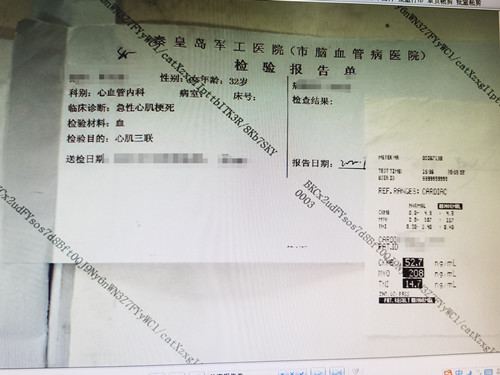

患者既往有高血压病史,每次出现胸骨后疼痛约20分钟后可逐渐缓解。王主任陷入深思:结合患者年龄、体重、病史,考虑并没有引起心梗的危险因素,而通过患者发病症状,易产生心脏神经官能症或急性胃炎导致误诊、漏诊。根据患者胸痛反复发作,导致胸痛持续不缓解,一定要仔细检查,正确判断。王主任立刻按胸痛中心诊疗流程为患者进行相关检查。果不其然,检查结果让人震惊,心电图提示:急性心肌梗死,立即住院治疗。入院后患者在第一时间得到治疗,胸痛症状逐渐缓解。